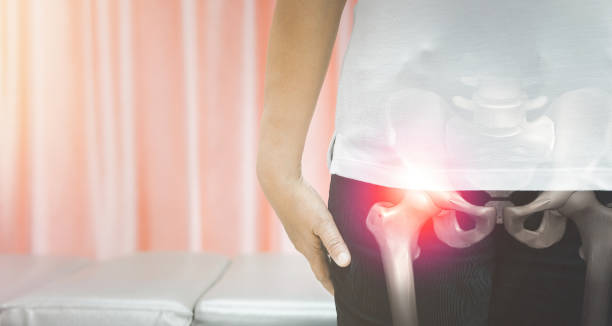

골반통증은 많은 사람들이 겪는 건강 문제 중 하나입니다. 장시간 앉아있거나 일을 많이 하다보면 골반 주변 근육이 약해지고 불균형해지는 경우가 많아 골반통증이 발생할 수 있습니다.

이런 골반통증의 경우 근육이 약해지거나 자세불량 등 다양한 이유가 있는데요.

이런 통증을 해결하기 위해서 스트레칭을 해주면 좋다고 합니다.